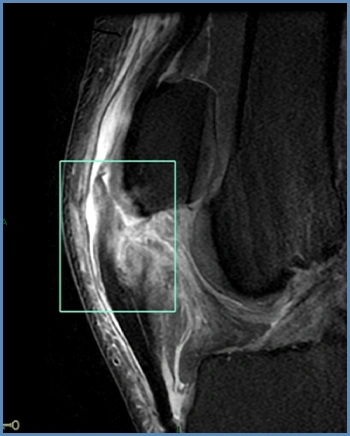

As reconstruções ligamentares são procedimentos cirúrgicos utilizados para reparar ou reconstruir os ligamentos do joelho lesionados, como o ligamento cruzado anterior (LCA), cruzado posterior (LCP) e lesões multiligamentares. Esses procedimentos geralmente envolvem a substituição do ligamento danificado por enxertos de tecido autólogo ou sintético, restaurando a estabilidade e função da articulação do joelho.

Lesões nos meniscos, que são estruturas em meia lua localizadas dentro das articulações do joelho. Elas são frequentemente causadas por movimentos de torção do joelho enquanto está carregando peso, como ocorre durante atividades esportivas. As lesões meniscais podem causar dor, inchaço ou travamento dos movimentos.